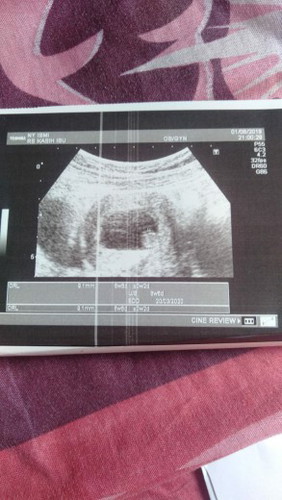

flek dan djj belum ada

Kali ini saya dibikin sedih bun.. Detak jantung janin belum ada:( sebelumnya saya ngeflek coklat, bsoknya priksa hasilnya begini.. Kata dokter disuruh kontrol satu minggu lagi.. Gimana solusinya ya bunda² Sedih bgt yg pasti akunya